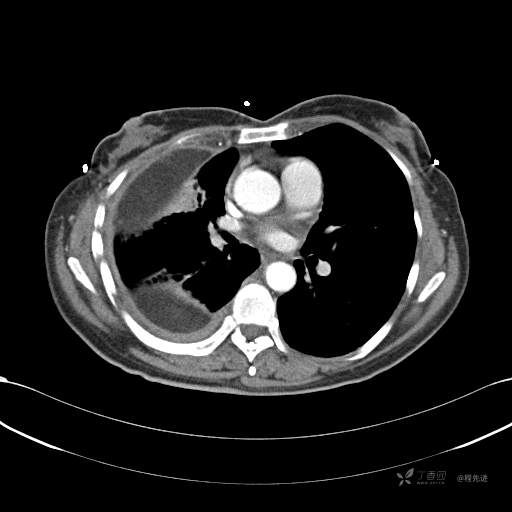

患者性别:女

患者年龄:51岁

简要病史:胸闷半年